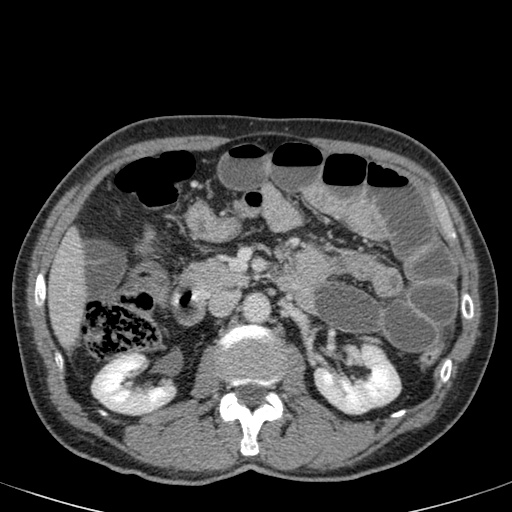

Đây là một bệnh nhân bị tắc ruột non.

Cuộn qua các hình ảnh.

Bạn có thể tìm thấy quai kín và nguyên nhân gây ra nó không?

Khi tiếp nhận bệnh nhân tại phòng cấp cứu với biểu hiện nghi ngờ tắc ruột non (SBO), điều quan trọng nhất chúng ta cần làm, ngoài việc chẩn đoán xác định, là xác định sự hiện diện hay vắng mặt của tình trạng thắt nghẹt.

CT là phương pháp chẩn đoán hình ảnh được lựa chọn trong đánh giá bệnh nhân nghi ngờ tắc ruột non.

Hình ảnh CT của tắc ruột non dạng quai kín phụ thuộc vào hai yếu tố:

- chiều dài đoạn ruột tạo thành quai kín

- hướng của quai ruột so với mặt phẳng tạo ảnh

Nếu quai kín ngắn và nằm trong mặt phẳng tạo ảnh, chúng ta sẽ thấy quai ruột hình chữ U hoặc chữ C.

Một hình ảnh quan trọng khác của tắc ruột dạng quai kín là các quai ruột non giãn xếp theo hình nan hoa với các mạch máu mạc treo hội tụ về một điểm trung tâm.

Hình ảnh này hầu như luôn do xoắn ruột non gây ra.